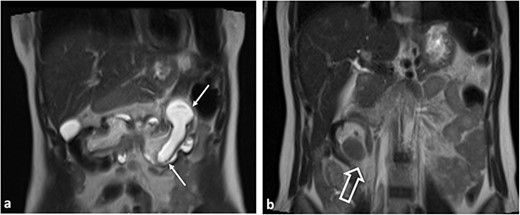

The radiologist’s description of the abdominal MRI with contrast has led to a suspicion of ‘intussusception’ in the transverse colon (Figs 2 and 3).

Sagittal T2WI MR images. Ileocolic intussusception (thick arrow).